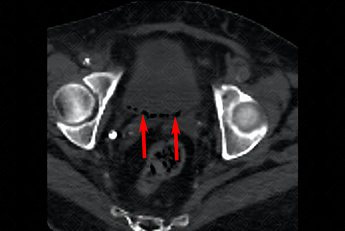

Texto alternativo para a imagem Créditos: Dra. Elazir Mota - Rio de Janeiro/RJ

Descrição da figura: Tomografia computadorizada do abdome superior e pelve evidenciando gás na parede posterior da bexiga (setas vermelhas), compatível com cistite enfisematosa.

• Tomografia computadorizada do abdome: Exame mais sensível para avaliar a presença de gás intraluminal ou intramural (f igura acima).